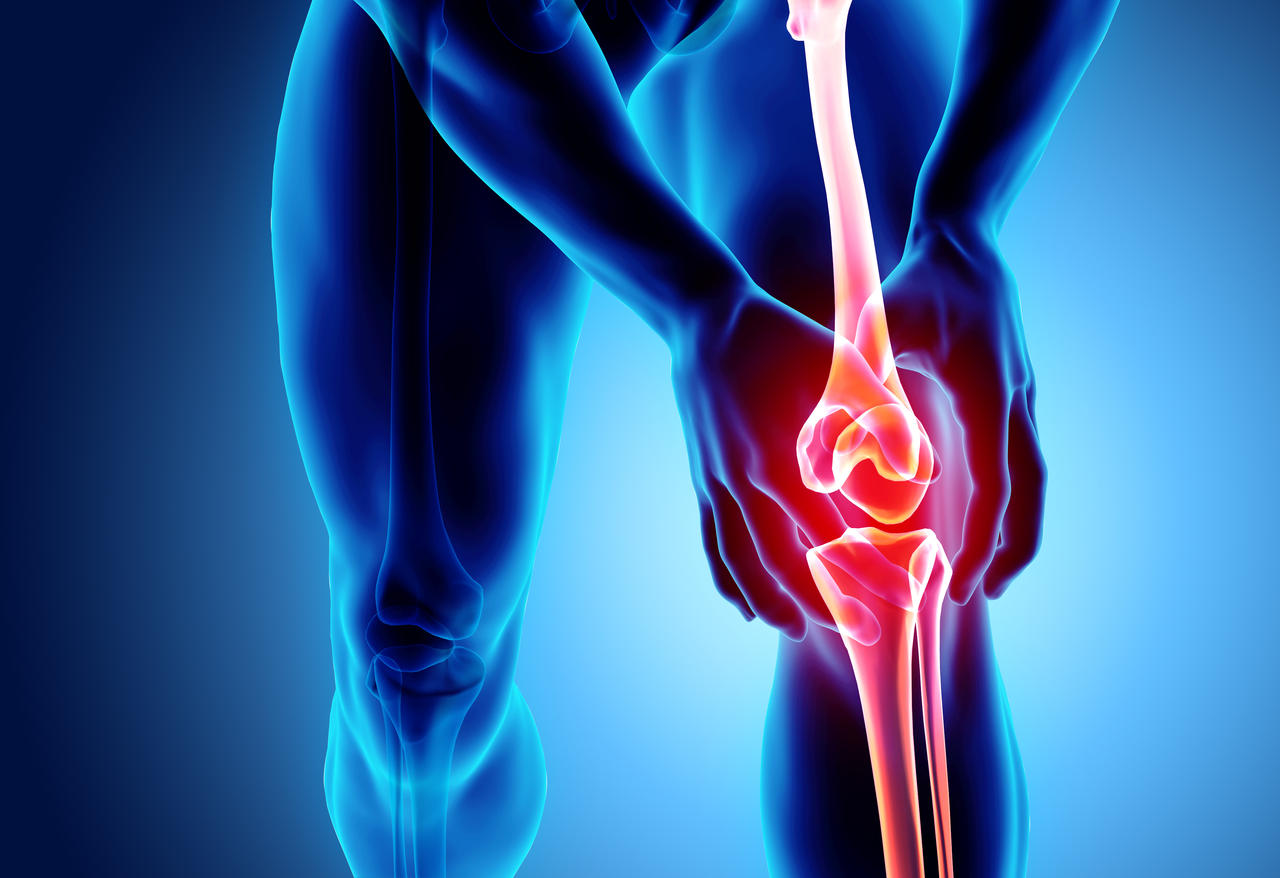

Sconsigliamo l’uso del tapis roulant

a tutti i pazienti che hanno avuto gravi lesioni ad anche,

ginocchia,

caviglie

o piedi.